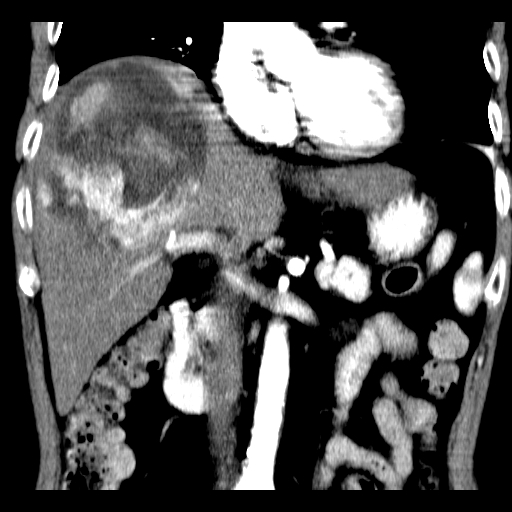

以下是引用卜一在2008-6-23 15:38:00的发言:[br]本例延时期的图象未扫完,单纯平扫 动脉期及门脉期特征分析:平扫低密度较大肿块,内见不规则出血灶,界限清楚。动脉期边缘结节样强化,门脉期病灶边缘进一步强化并范围明显缩小。因此考虑:血管瘤伴出血!

以下是引用深泽交通医院在2008-6-23 16:40:00的发言:[br]考虑肝癌伴出血.诊断依据:平扫瘤壁结节密度低于肝实质,动脉期壁结节明显强化,门脉期略低于肝实质密度[br]病灶有明显的假包膜,